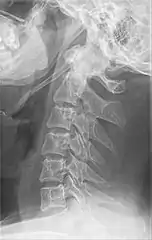

Radiograph, lateral view showing elongated stylohyoid process and stylohyoid ligament ossification

Radiograph, lateral view showing joint-like formation in ossified stylohyoid ligament

Imaging is important and is diagnostic. Visualizing the styloid process on a CT scan with 3D reconstruction is the suggested imaging technique.[12] The enlarged styloid may be visible on an orthopantogram or a lateral soft tissue X ray of the neck.